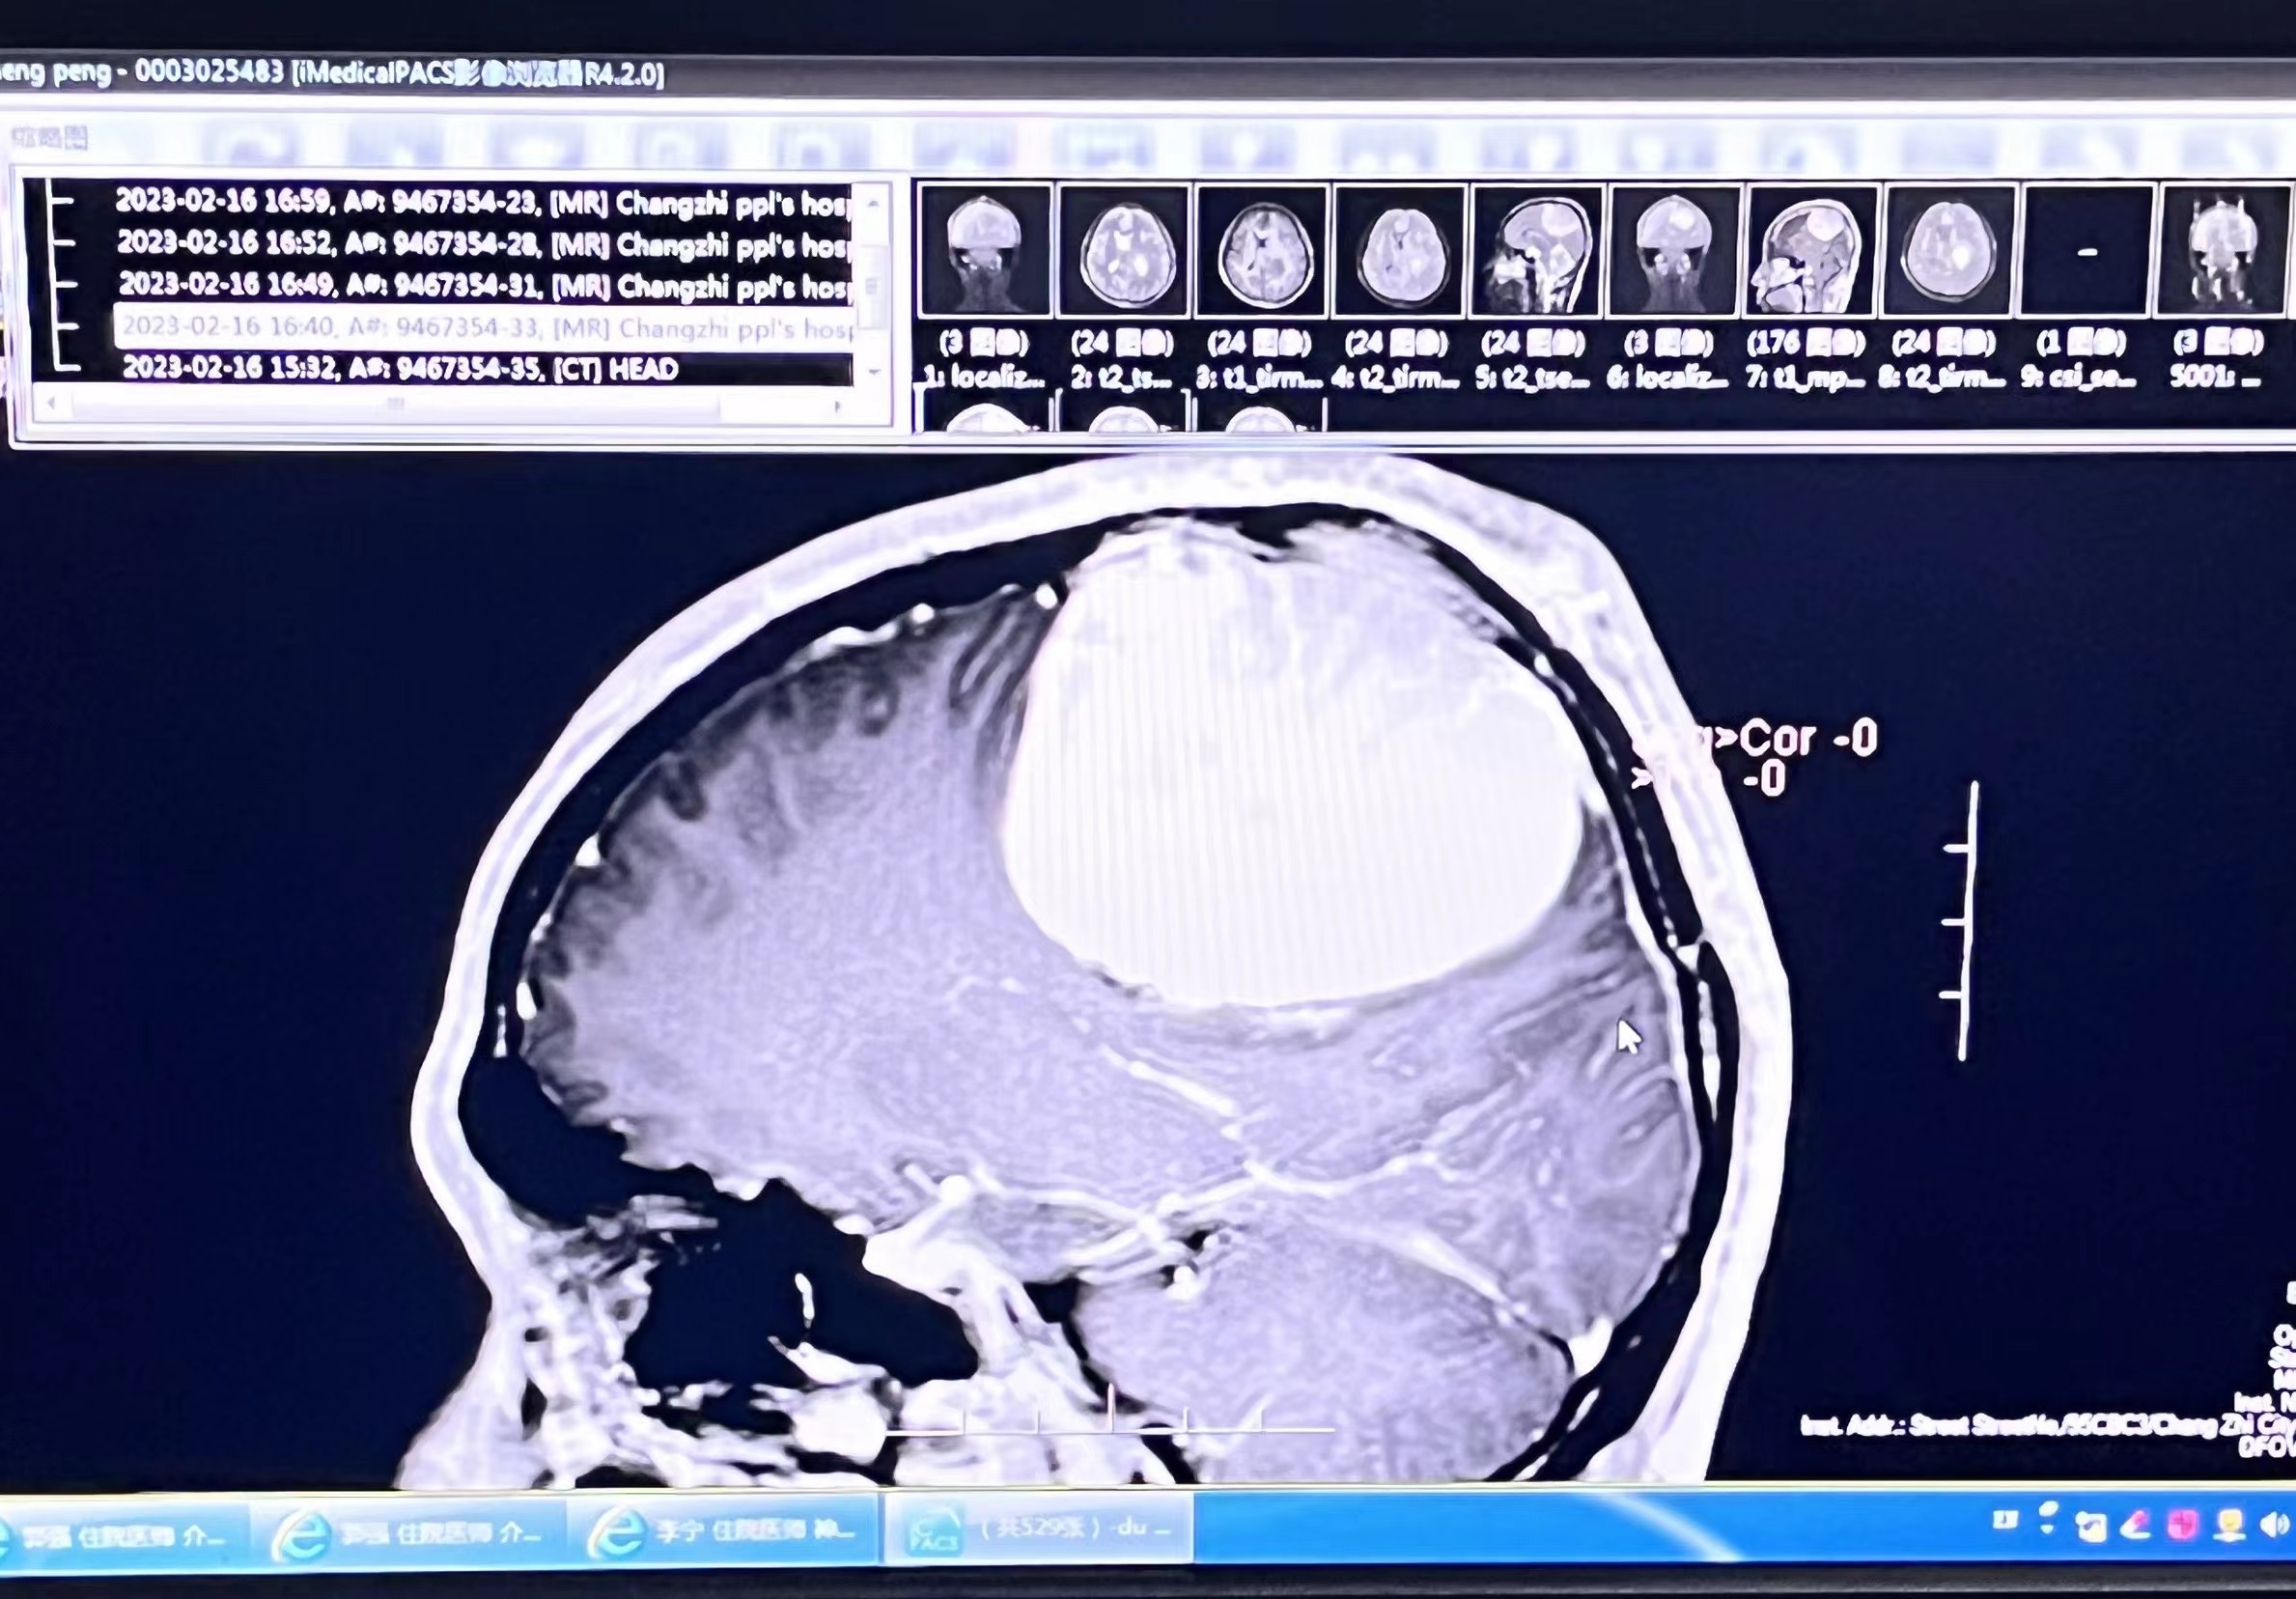

25岁的小赵头晕头疼已有数月,住院治疗无好转,且症状不断加重,甚至出现半侧肢体无力等异常情况。经影像检查提示为左侧优势半球中央前后回上方有一个约10公分鹅蛋大小的窦镰旁脑膜瘤,肿瘤位置深,与中线处的上矢状窦、中央沟静脉及大脑前动脉关系密切,因此如何能够将肿瘤完全切除,同时不损伤其周边重要的皮层及血管,就变得极其关键。种种症状都表明这是一台难度极大风险极高的手术!如此巨大的肿瘤若不尽快采取措施很可能诱发脑疝危及生命。

影像检查提示脑膜瘤位置